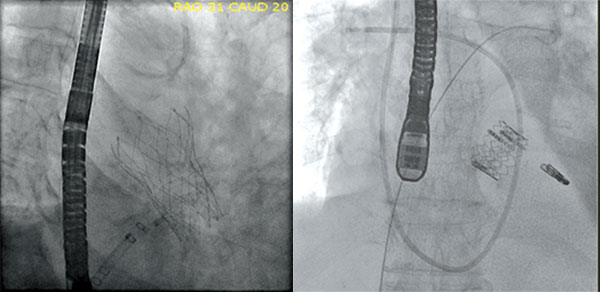

Case Study

A female patient in her 50s underwent mantle field radiation for lymphoma as a child. She subsequently developed aortic stenosis and left main coronary artery stenosis. The patient’s left main lesion was addressed with a stent and an LVAD in the event she became hypotensive during the procedure, which could be fatal. Following recovery from this procedure, she then underwent TAVR with excellent results.

Stent and LVAD Placement

TAVR